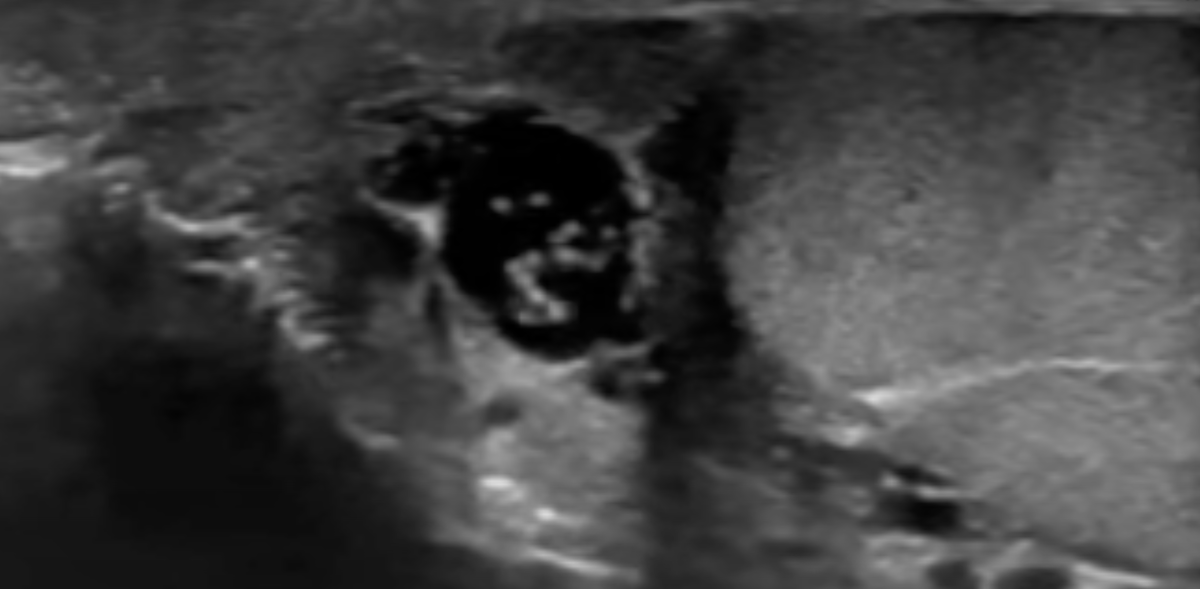

Лаборанты определили повышенное содержание в крови мужчины эозинофилов – лейкоцитов, основная функция которых заключается в борьбе с многоклеточными паразитами. В тканях мошонки УЗИ-специалисты обнаружили «движущиеся линейные структуры». Эффект движения паразитов врачи назвали «филяриальным танцем».